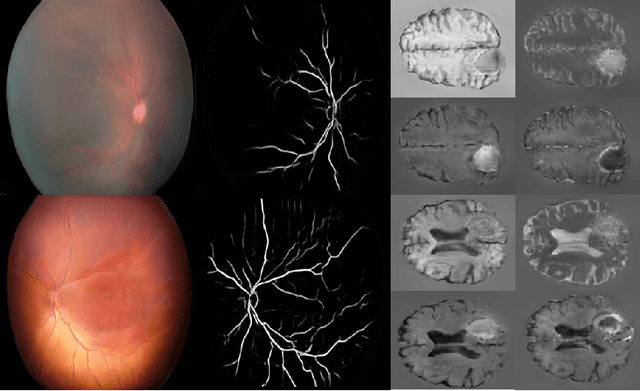

Abstract:Generative adversarial networks (GANs) are a class of unsupervised machine learning algorithms that can produce realistic images from randomly-sampled vectors in a multi-dimensional space. Until recently, it was not possible to generate realistic high-resolution images using GANs, which has limited their applicability to medical images that contain biomarkers only detectable at native resolution. Progressive growing of GANs is an approach wherein an image generator is trained to initially synthesize low resolution synthetic images (8x8 pixels), which are then fed to a discriminator that distinguishes these synthetic images from real downsampled images. Additional convolutional layers are then iteratively introduced to produce images at twice the previous resolution until the desired resolution is reached. In this work, we demonstrate that this approach can produce realistic medical images in two different domains; fundus photographs exhibiting vascular pathology associated with retinopathy of prematurity (ROP), and multi-modal magnetic resonance images of glioma. We also show that fine-grained details associated with pathology, such as retinal vessels or tumor heterogeneity, can be preserved and enhanced by including segmentation maps as additional channels. We envisage several applications of the approach, including image augmentation and unsupervised classification of pathology.